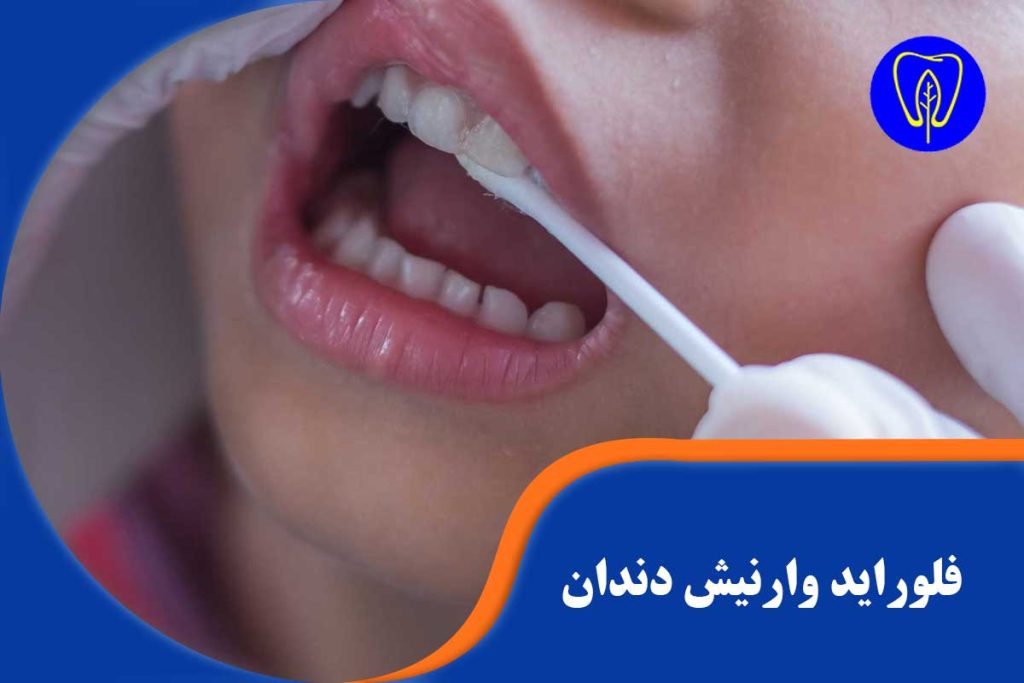

- اعمال وارنیش: سپس، با استفاده از یک قلمموی کوچک یا براش مخصوص، فلوراید وارنیش که حالتی شبیه به یک لاک یا چسب دارد، روی سطح تمام دندانها (جلو، پشت و سطح جونده) به سرعت و به صورت لایهای نازک مالیده میشود. این ماده در لحظه با بزاق دهان واکنش داده و خشک میشود.